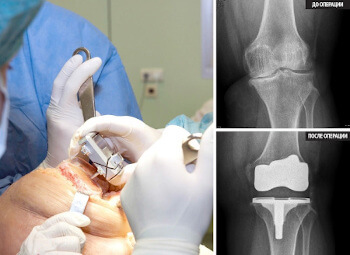

La endoprótesis de las articulaciones es muy cara, y una operación muy seria.

Endoprótesis de rodilla, foto

La endoprótesis de las articulaciones es muy cara, y una operación muy seria.

Endoprótesis de rodilla, foto